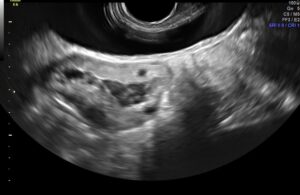

- Aspiração do conteúdo do cisto com uma agulha de 35 cm, guiado por ultrassonografia transvaginal. A mesma agulha que utilizamos na aspiração de oócitos nos procedimentos de reprodução assistida;

- Lavagem da cavidade do cisto com soro fisiológico 0,9% múltiplas vezes, até a saída de líquido claro;

- Aplicação do álcool absoluto na cavidade do cisto. O volume de álcool é sempre 60% do volume inicial do endometrioma.

- O álcool deve ficar pelo menos 10 minutos na cavidade do cisto.

- Aspiração do álcool e retirada da agulha.